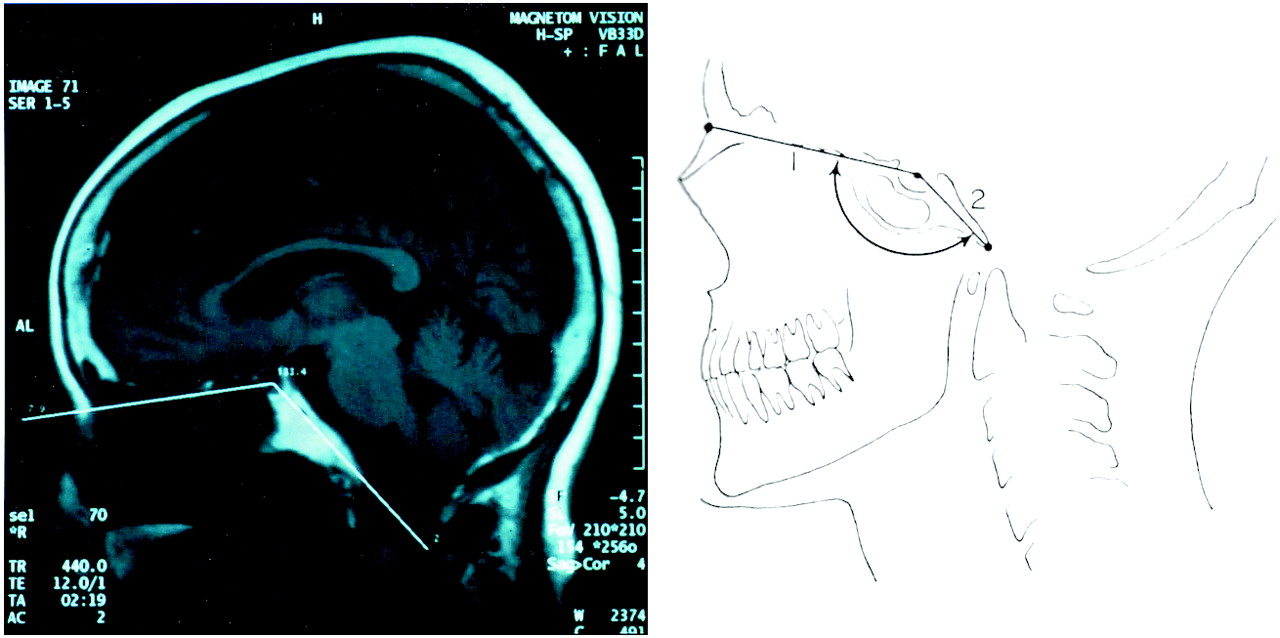

• The skull base angle is formed by a line joining the nasion with the centre of the pituitary fossa and a line joining the anterior border of the foramen magnum with the centre of the pituitary fossa.

• Basilar kyphosis is present if it is less than 125°.

• Normal clival angle (top) measured by the NTB angle of Welcker joining the nasion (N), tuberculum (T) and basion (B).

The angle should be < 130°.

• Platybasia (middle) is marked by an increased NTB angle. This raises the basion and forces the foramen magnum plane (dotted line) to tilt upwards. (skull base angle>145°)

• The same upward tilt of this plane also occurs with a short clivus (lower)